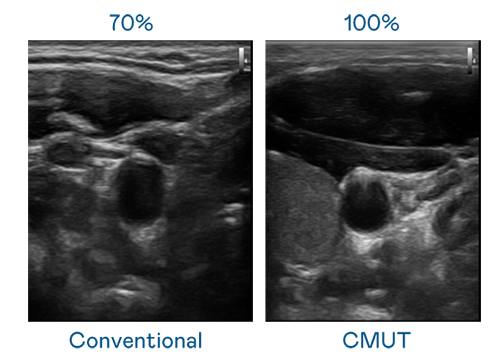

CMUT 技術是一種用電容式微機電元件來產生超音波訊號的技術。與傳統 PZT 壓電式技術相比,CMUT 頻寬增加 30%,更寬頻的超音波訊號讓影像解析度大幅提升,是實現高影像品質醫療超音波掃描、促進精準醫療發展的關鍵技術。

大頻寬帶來超清晰影像

超音波影像的解析度高低,首先取決於探頭能發出的訊號頻寬。利来国际 CMUT 可提供高清晰的超音波訊號,提供高頻寬、高靈敏度、影像紋理細節更高的超音波影像,協助醫護人員縮短影像判讀時間及利用精準的醫療影像進行診斷。